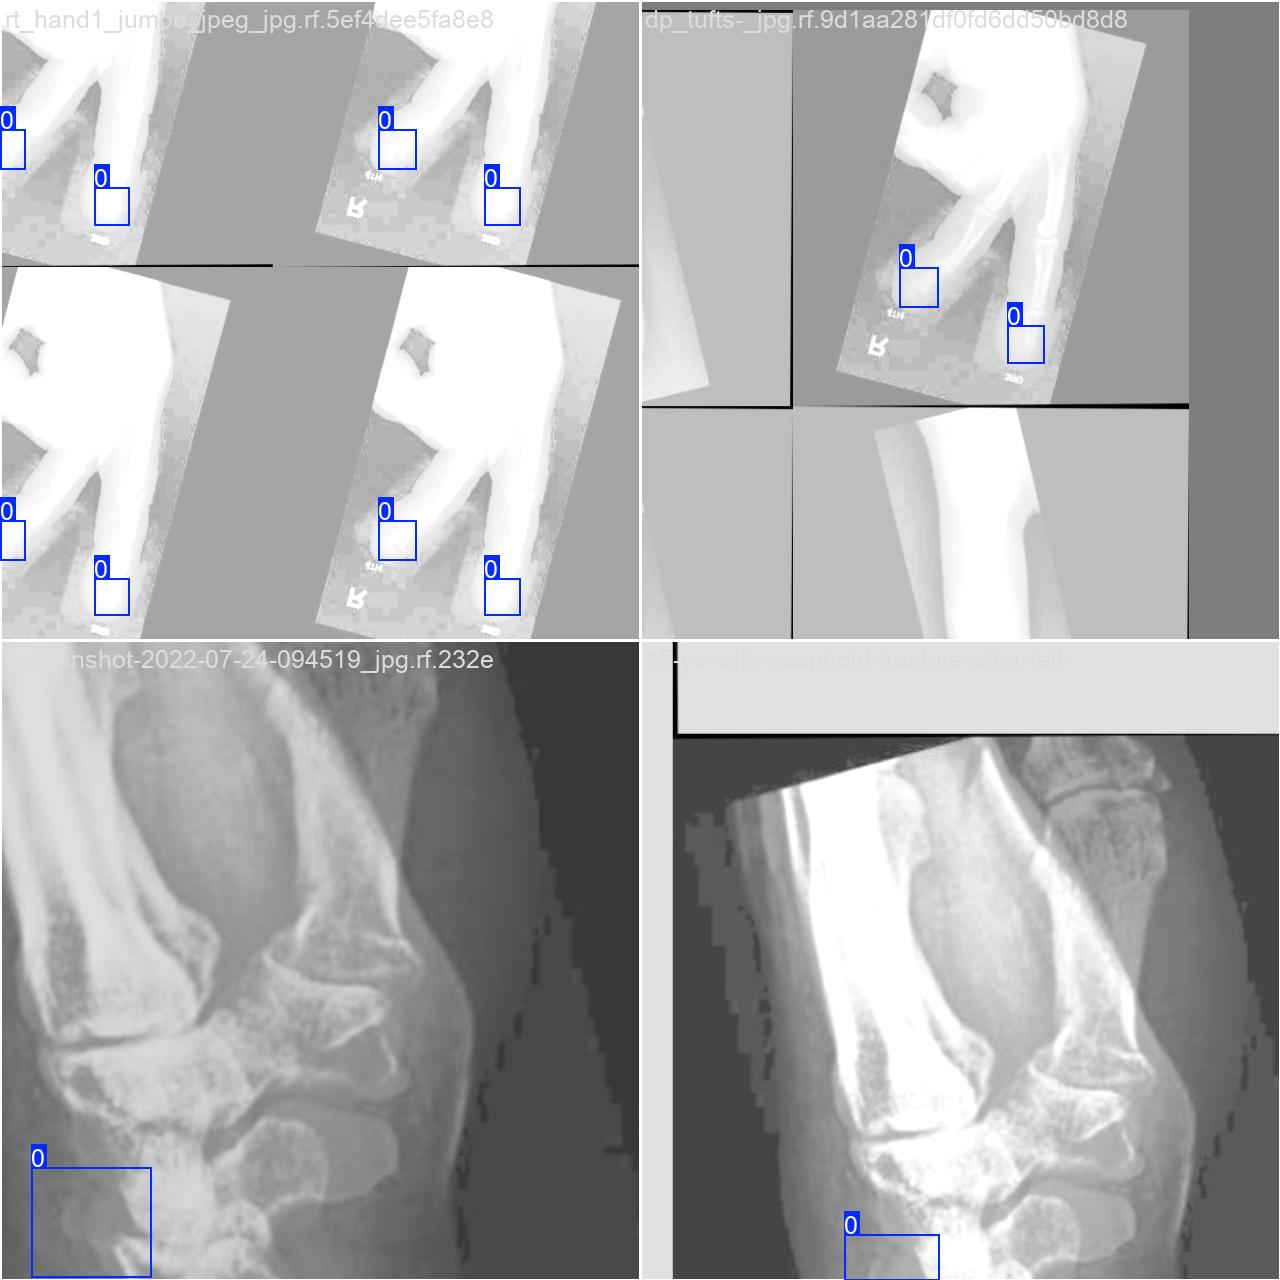

本研究使用了包含各种骨折相关图像的数据集,并通过Labelimg标注工具对每张图像中的目标边框(Bounding Box)及其类别进行标注。然后主要基于YOLOv8n这种模型进行模型的训练,训练完成后对模型在验证集上的表现进行全面的性能评估及对比分析。模型训练和评估流程基本一致,包括:数据集准备、模型训练、模型评估。本次标注的目标类别为骨折,数据集中共计包含10412张图像,其中训练集占9122张,验证集占843张,测试集占447张。部分图像如下图所示:

部分标注如下图所示: